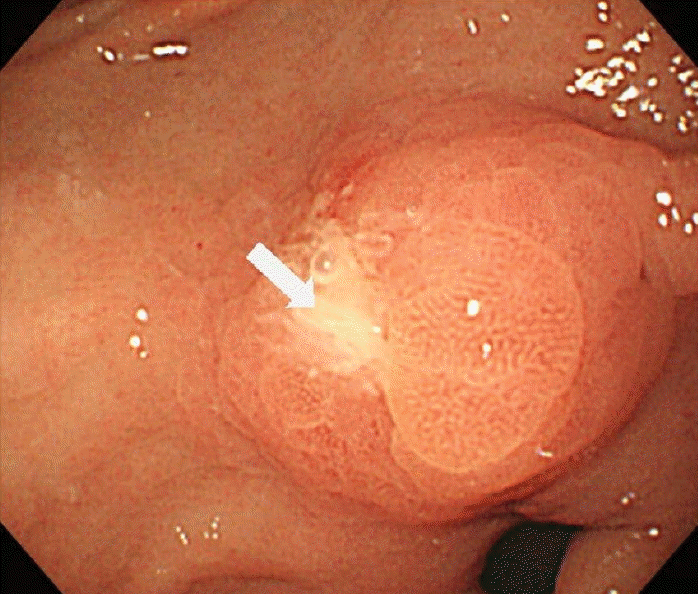

Figure 2.

In the first case, a small ulcerative lesion with edematous mucosa on the prepyrolic area of the antrum was seen.